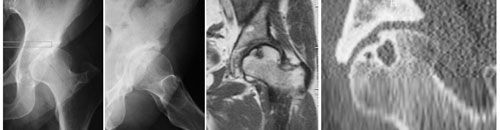

Actualité Arthroscopie, butée et forage : un cas de chirurgie conservatrice de la hanche par voies d'abord minimales , Philippe Chiron Hôpital Pierre-Paul Riquet, Toulouse, France N°123 - Avril 2003 ● 19 min de lecture